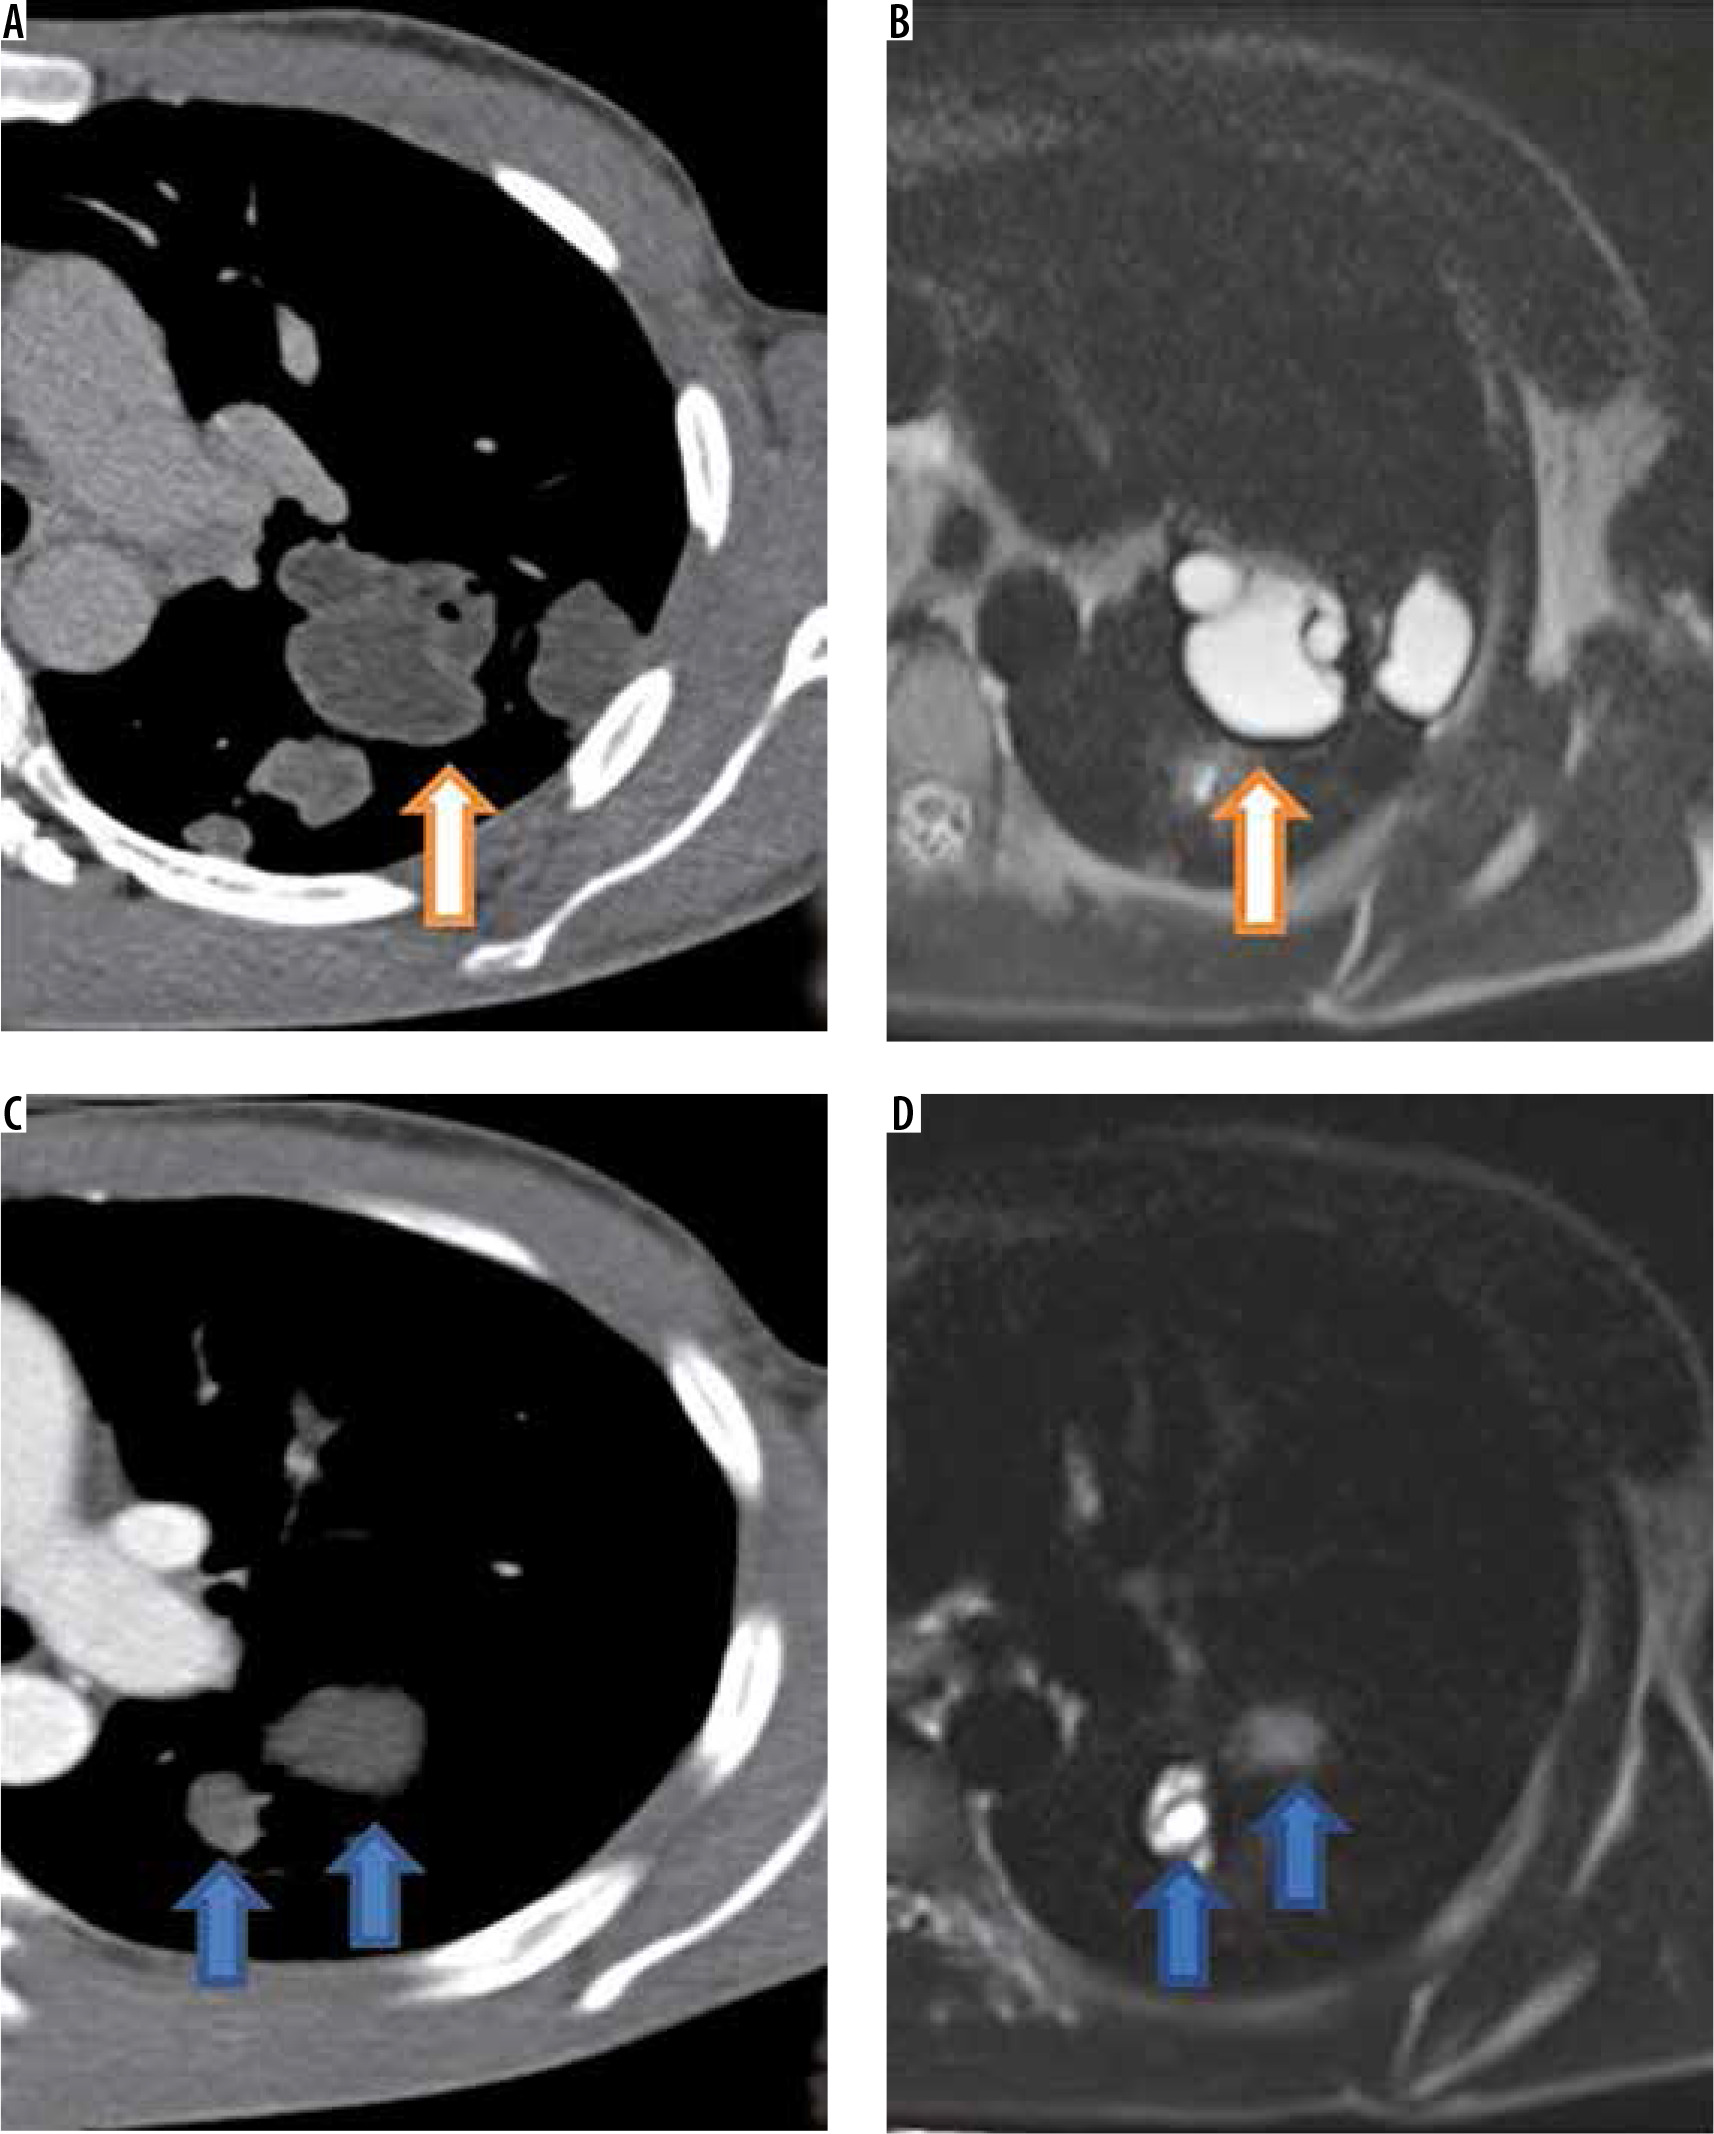

One patient with multiple cysts in parenchyma of both lungs was also found to have intra-vascular hypodense material in right pulmonary artery and left upper lobar pulmonary artery suggestive of intravascular embolisation of hydatid cysts. This patient had right pulmonary artery occlusion with hypertrophied bronchial, intercostals, and right inferior phrenic artery (Figure 4). CT findings are given in detail in Table 1.

Figure 4

Intravascular pulmonary hydatid cyst in right main and left branch pulmonary artery. Axial (A) and coronal (B) computed tomography (CT) images reveal hypodense filling defects in right main pulmonary artery with extension into right upper lobar pulmonary artery with air foci inside (arrows in A and B). Coronal T2-W image (E) shows multiple cysts corresponding to right main and upper pulmonary lobar artery suggesting diagnosis of intravascular hydatid cysts. The patient showed hypertrophied intercostal (C), bronchial and inferior phrenic arteries. Axial CT image (D) in the same patient also shows left branch pulmonary artery hypodense filling defect which was hyperintense on T2-W image (F)

Pulmonary hydatid disease is more frequently encountered in children [10]. Right lung is involved more frequently than left lung [2,3]. With regards to location, lower lobes are affected more than upper lobes [2,3]. On CT hydatid cysts exhibit a variety of appearances. Unruptured cyst appears as a smooth hypodense cystic lesion with a well-defined perceptible wall [2,3]. Some cysts can have a thin imperceptible wall. However, when a cyst undergoes a complication like rupture or infection it assumes different appearances on CT. Thick-walled cyst with a wall thickness of greater than 10 mm can be seen in infected cysts [11]. When a growing cyst erodes an adjacent bronchus air tracks between ectocyst and exocyst and gives rise to an air crescent sign. If the air dissects between the ectocyst and exocyst for a large part of circumference of cyst the air seeps both inside the endocyst and between the endocyst and pericyst forming parallel air shadows, it is referred to as onion peel or cumbo sign [3,12]. When the endocyst becomes detached and floats within the cyst it produces water lily or Camelotte sign [3]. Sometimes the contents of a cyst may be emptied into the bronchus and coughed out by the patient, leaving behind an air-containing cyst, called empty (dry) cyst sign [2]. When these typical signs are seen on CT the diagnosis may be straightforward. However, a complicated cyst that has undergone rupture or infection does not always give rise to classical signs. On many occasions complicated cysts give rise to bizarre appearances [13]. A complicated cyst with air fluid level, thicker irregular wall, and surrounding consolidation can masquerade as lung abscess, necrotic lung cancer, cystic metastasis, necrotising pneumonia, or a schwannoma with cystic degeneration [14-16]. On CT we could correctly make a diagnosis of hydatid cyst in 68 (80.9%) patients, and 16 (19.1%) cases with atypical appearance on CT were wrongly given an alternate diagnosis. Involvement of the pulmonary arteries with hydatid cysts is a very rare occurrence and has been proposed to represent embolisation of daughter cysts from other organs like the liver [17-19]. We observed pulmonary artery involvement in 2 cases. One had complete occlusion of the right pulmonary artery and its upper lobar branch. The patient had also involvement of the left upper lobar pulmonary artery (Figure 4). With regards to multiplicity and location of lesions, our observations are in tune with previous reports in literature [3]. Owing to the compressibility of lung tissue hydatid, cysts can grow to large sizes (up to 20 cm). The largest cyst in our series was 16 cm. The term giant pulmonary hydatid cyst is loosely used for cysts that are more than 10 cm in size. None of the cysts in our study showed calcification or daughter cysts, although they have been reported previously [3]. In contrast to the extra-pulmonary cysts, pulmonary hydatid cysts seldom show calcifications or daughter cyst formation [20,21]. It is believed that a low concentration of carbon dioxide within the pulmonary parenchyma decreases the serum calcium level, which retards the precipitation of calcium in dead or degenerated tissue [4].